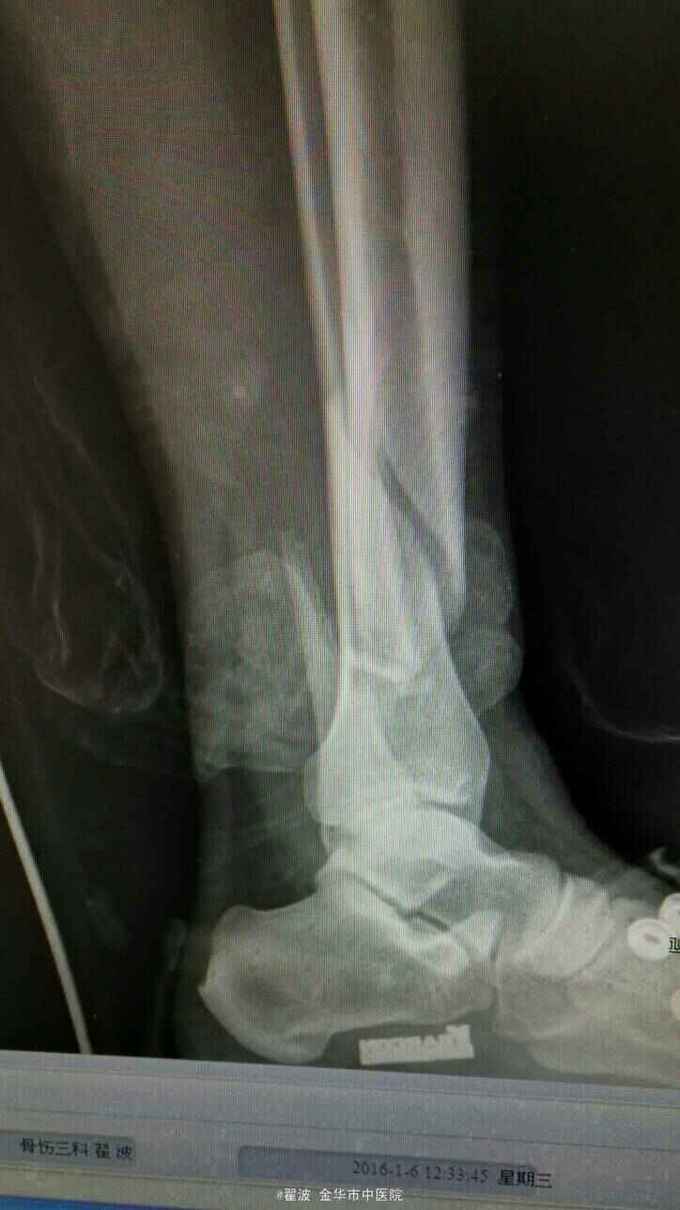

主诉:高处坠落致右小腿肿痛活动受限2小时 病史:患者2小时前从2米高处摔下,致右小腿疼痛,局部肿胀,活动受限。由家人送至我院急诊就医,摄片提示右胫腓骨粉碎性骨折,遂收住入院,入院后予抬高患肢,石膏固定,冰敷。

查体:右小腿下段肿胀明显,皮肤无破损,压痛阳性,可及骨擦感,并有异常活动,右下肢轴向叩击痛阳性,肢端感觉及血运正常,踝关节活动受限。

伤后肿胀很明显,可见张力性水泡,出现皱褶才手术。